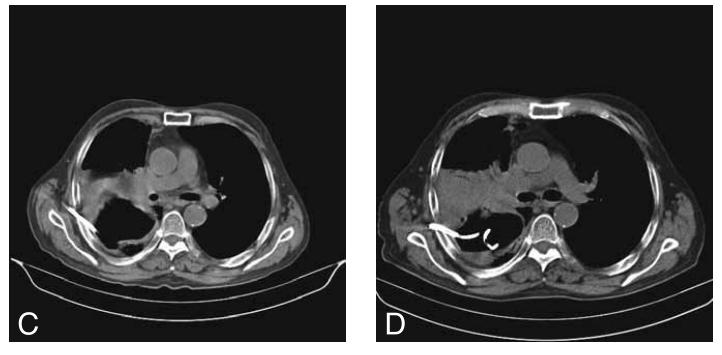

42岁男性,发热,肺脓肿。

美罗培南和万古霉素进行抗生素治疗。持续5天的抗生素治疗,没有显示出令人满意的临床结果。

在CT引导下,在肺脓肿里面放入10Fr猪尾导管,然后引流肺脓肿。然而,只排出42毫升脓液。患者仍然发热,肺部的病灶还增多了。

图11

换大号引流管,直接上28Fr猪尾导管,是以前的大约3倍。

患者上着呼吸机,搞个全麻,双腔管单肺通气,隔离左肺(防止脓液进入),在X线引导下放入大号引流管。

图12

负10cmH2O的压力吸引,8天引流出650毫升脓液,脓液检测到口腔普氏杆菌、血管链球菌和坏死梭杆菌,抗生素治疗降级为舒巴坦钠/氨苄西林钠,5天后脱离呼吸机,第18天取出导管,40天后出院。

7个月后,他的胸部CT证实肺脓肿完全治愈,但遗留了一个薄壁空洞。